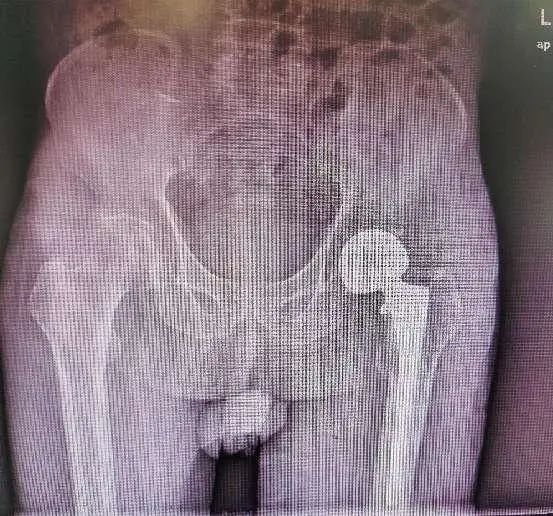

曾在美国华盛顿费尔法克斯医院及安德森骨科医院进修人工关节置换与翻修,曾在南方医科大学第三附属医院(广东省骨科医院、广东省骨科研究所)工作和学习。一直从事骨科临床、科研及教学工作。熟悉骨科前沿新技术及其应用,对实现骨科患者术后无痛及快速康复有深入研究。熟练掌握各种骨关节疾病,包括老年性退行性髋膝骨关节炎、成人股骨头坏死、髋关节发育不良及关节内外畸形、髋部骨折(股骨颈及股骨粗隆间骨折)、类风湿性关节炎;髋膝关节感染后遗症、人工髋、膝关节假体感染翻修手术、人工髋、膝关节假体骨折翻修术,微创前路的全髋关节置换术;运动创伤所导致的关节损伤,包括膝关节半月板、交叉韧带、侧副韧带损伤,肩关节肩袖和关节盂唇损伤。熟练掌握小切口髋、膝人工关节置换手术,关节镜下半月板及韧带的修复术。发表SCI论文和中文核心期刊论文多篇,参与省级及市级课题多项。